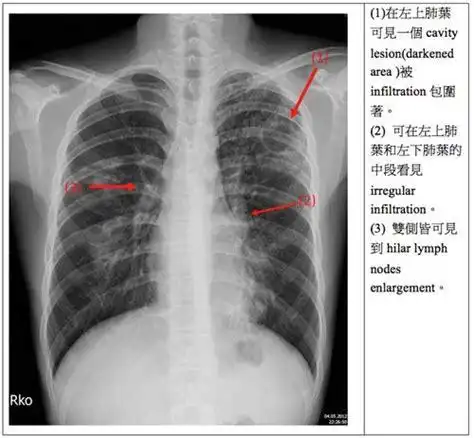

一例教科书级胸片:典型"陈旧性肺结核"

每周胸片92期观影识病肺结核病治疗过程系列片如何描述和诊断

肺结核. 旧病人的胸部x线片

各型肺结核的典型影像表现

肺结核在胸片上的表现